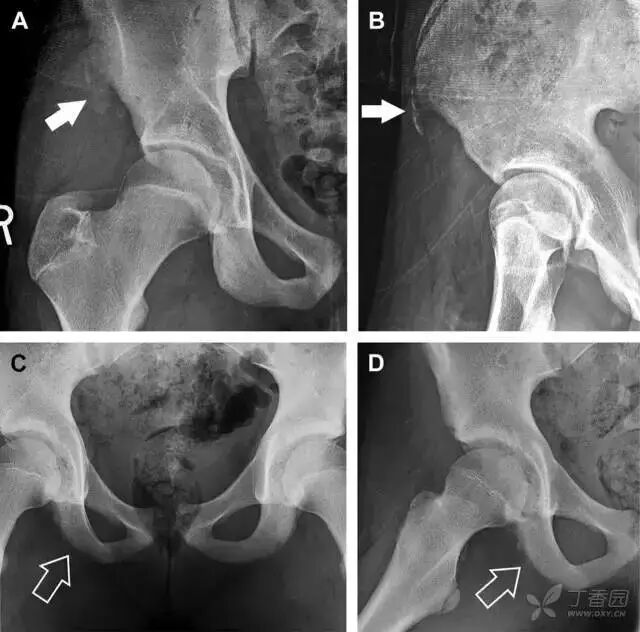

耻骨骨折

具有持续损伤因素的耻骨支骨折,可能看似轻微,尤其是合并骨质疏松的患者。因此,特别需要注意皮质缺损和骨密度改变。长跑运动员易发生耻骨应力性骨折,常常发生在靠近耻骨联合的下支。由于这些骨折为非移位骨折,所以常常被忽视。

图 3 自行车事故患者,侧方受力的髋臼前柱/耻骨骨折。A 正位平片示右侧髂耻线轻微中断(实箭头),此处异常最初并未发现。此外,右下方其实还有一处轻微耻骨支骨折(空箭头)。B 10 天后行骨闪烁显像证实了髋臼前柱骨折和侧耻骨下支骨折(箭头)。值得注意的是,左侧前柱亦存在异常

儿童撕脱性骨折

撕脱性骨折常在体育运动时由于肌肉强烈收缩引起。图 4 为容易发生儿童撕脱性骨折的部位。

图 4 儿童撕脱性骨折的危险区

图 5 儿童撕脱性骨折。正位片(A)和斜位片(B)示从髂前上棘撕脱的骨折碎片(箭头)。正位片(C)和另一个患者的蛙式位片(D)示右侧坐骨支皮质毛糙,腘绳肌腱撕脱损伤(如 C 和 D 空箭头所示)